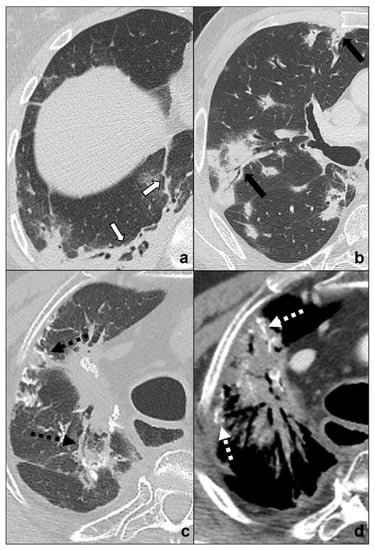

- generally focal entities, appearing as a single nodule (<3 cm) or mass (>3 cm) with invasive and infiltrative features;

- spiculated margins with pleural and parenchymal retraction stripes causing extensive pulmonary distortions and mediastinal attraction;

- inhomogeneous density in relation to hemorrhagic and/or necrotic foci (e.g., small cell carcinoma, large cell carcinoma);

- inhomogeneous contrast enhancement that is typical of cancer and is not seen in COVID-19 consolidations;

- possible endobronchial growth and spread through airspace (STAS), which has been recognized as a feature with prognostic significance in 2021 WHO classification of thoracic tumors;

- not generally associated with ground-glass or crazy paving areas. If ground-glass or crazy paving areas are present due to edema and hemorrhage, they do not follow COVID-19 pneumonia phases;

- may be central or peripheral, but do not present a strictly subpleural distribution (squamous cell carcinoma and small cell carcinoma being generally central tumors whilst large cell carcinoma being often peripheral);

- cysts and/or cavitations (squamous cell carcinoma);

- chest wall, mediastinum and mediastinal organs invasion (frequent in small cell carcinoma, which is most common oncological cause of superior vena cava compressive/infiltrative/thrombotic obstruction);

- associated findings such as atelectasis (Figure 5d) and post-obstructive pneumonia (typical of endobronchial growing tumors such as squamous cell carcinoma;

- lymphangitis carcinomatosis;

- mediastinal lymphadenopathies and pleural effusions;